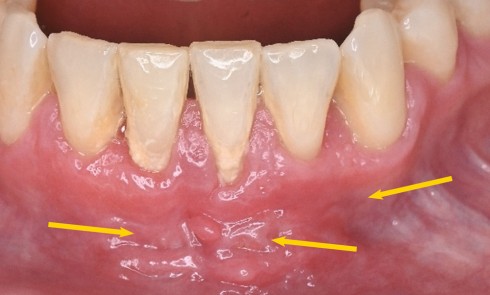

Quelles sont les 7 formes cliniques des épulis ? 1. Épulis inflammatoire (plasmocytaire) Nodule indolore, pédiculé, érythémateux, parfois ulcéré (fig. 1a)....